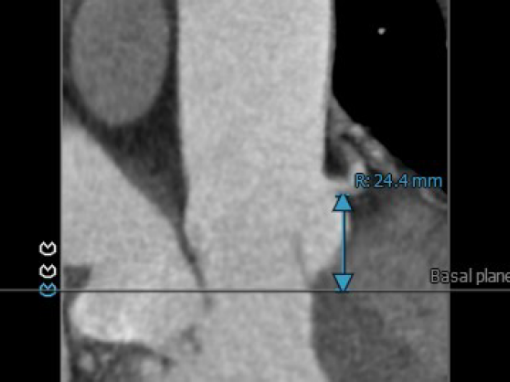

3.双侧冠脉开口高度可 LCA:18.5mm,RCA: 24.4mm;

右冠高度:24.4mm